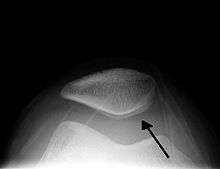

| A traumatic right knee effusion; note the swelling lateral to the kneecap as marked by the arrow | |